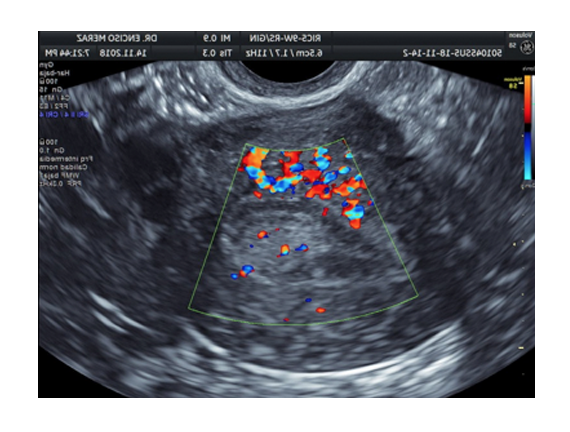

ENDOMETRIOSIS

Es una enfermedad benigna crónica que afecta al 10-15% de mujeres en edad reproductiva. Consiste en la aparición y crecimiento de tejido endometrial, el cual recubre el interior del útero, en otras localizaciones fuera de la cavidad uterina.